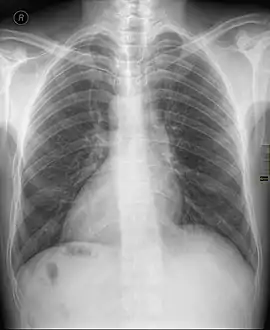

![]() أشعة سينية لشخص مصاب بالقلب اليميني و تظهر قمة القلب في اليمين أشعة سينية لشخص مصاب بالقلب اليميني و تظهر قمة القلب في اليمين | |